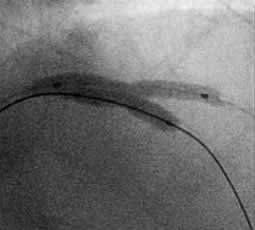

A-7 : 6 months follow-up angio

![]() Stent LAD: 3.5mm/15mm Diagonal: 2.5mm/18mm |

![]() KBT LAD: 3.5mm Diagonal: 3.0mm |